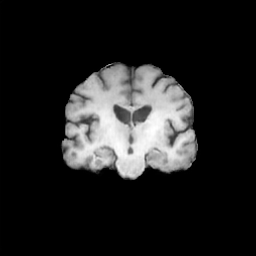

The results presented in Table 1 and 2 show our proposed method’s performance on unconditional 3D brain MR and chest CT image generation. Our proposed approach not only outperforms most comparing methods in FID and MS-SSIM metrics, it also has the lowest inference GPU memory footprint at a resolution of and was the only diffusion-based method that could be trained at a resolution of . Operating in the wavelet domain and profiting from the reduced spatial dimension also results in a relatively short inference time of / at the respective resolutions. Compared to the results presented in [23], we did not find that incorporating wavelet information into the network’s feature space (WavU-Net) increased the model’s performance. Qualitative results of our proposed method (WDM) are shown in Fig. 2 and 3. A qualitative comparison of samples produced by all evaluated methods can be found in the Supplementary Material.

We demonstrate our model’s performance on two publicly available datasets: BraTS 2023 Adult Glioma [1, 2, 15, 20] and LIDC-IDRI [14]. For training on the BraTS dataset, we use the T1-weighted brain MR-images, clip the upper and lower 0.1 percentile intensity values, zero pad the volumes to a size of and normalize them to a range of . For training on the LIDC-IDRI lung CT dataset, we initially clip all values below and the upper 0.1 percentile intensity values. We then resample the images to an isotropic voxel size of 1 , center crop them to a size of , and normalize to a range of . When training on images with a resolution of , we perform downsampling by applying average pooling.